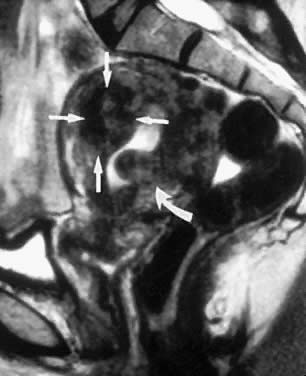

MRI is a highly accurate technique for evaluating uterine leiomyomas, adenomyosis, and uterine anomalies.13–15 T2-weighted images clearly delineate the myometrium, junctional zone, and endometrium, allowing highly accurate mapping of the size, location, and degree of myometrial involvement of uterine leiomyomas (Figs. 4 and 5). It is much more accurate in identifying and mapping adenomyosis. The major limitations of MRI imaging are cost and delays in scheduling examinations.

Fig. 4. This sagittal magnetic resonance image shows an anterior intramural leiomyoma (straight arrows) and a submucous leiomyoma (curved arrow). The intramural leiomyoma is category T-II, with more than 50% penetration toward the endometrial cavity. The submucous leiomyoma is category T-I, with less than 50% extension toward the uterine serosa.